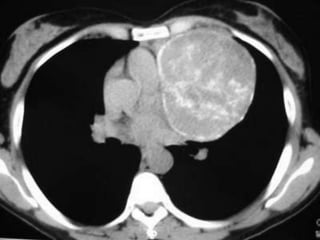

SEMINOMAS

• Ubicación: mediastino anterior

• Edad: 30 años

• Clínica: por efecto de masa

• Diagnóstico:

– PAAF

– GCH aumentada en 10%

– Alfafetoproteína siempre negatina

• Tratamiento: QTX + RTX + cirugía de lesiones residuales con

excelente respuesta

SEMINOMAS • Ubicación: mediastinoanterior • Edad: 30 años • Clínica: por efecto de masa • Diagnóstico: – PAAF – GCH aumentada en 10% – Alfafetoproteína siempre negatina • Tratamiento: QTX + RTX + cirugía de lesiones residuales con excelente respuesta